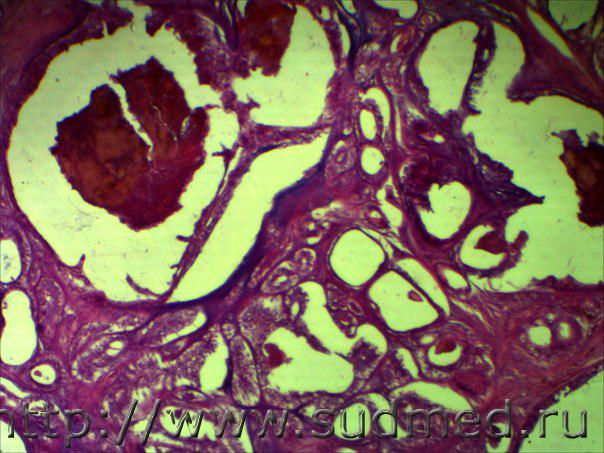

в области молочной железы у суки внутрипротоковый рак или же аденокарцинома из сальных желез ?

Похожи на внутри протоковый рак.

Я бы добавил,что это инвазивный....